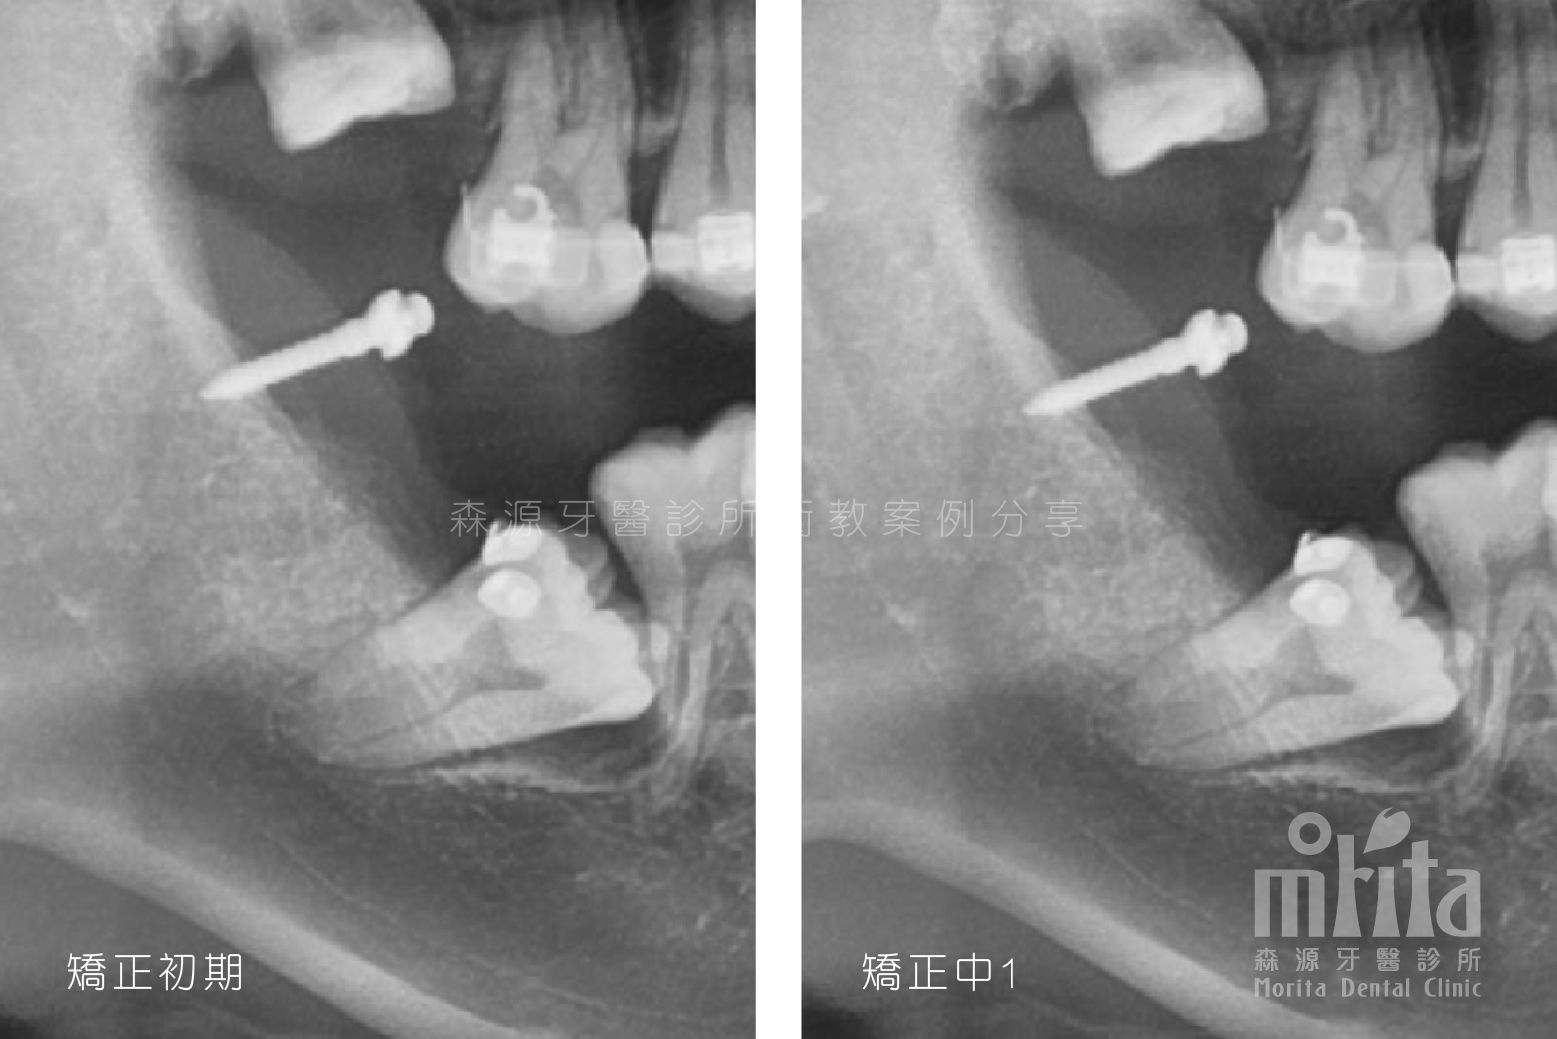

阻生齒 Impaction

可能因為過早地缺牙,可能因為齒列過於擁擠,又或是老天爺開的玩笑,造成有些該⻑出來的牙齒⻑不出來,需要在阻生齒還有生⻑潛力時拉一把,讓牙齒順利萌發。